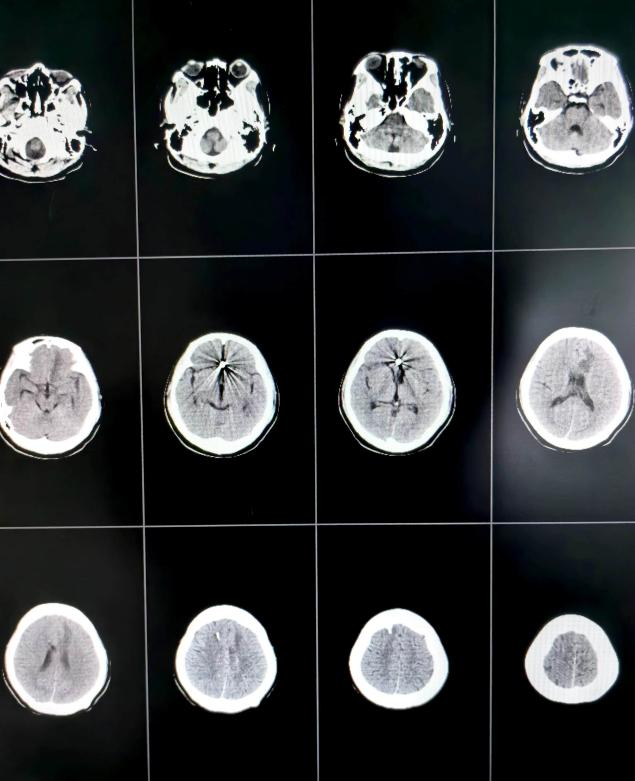

术后第13天头颅CT示颅内出血引流完全,脑室无扩大

由于患者意识昏迷状态,自主呼吸弱,给予气管插管呼吸机辅助呼吸,护理团队给予患者特级护理,进一步引流颅内积血及血性脑脊液,术后第3天再给患者行腰大池引流术。在神经外科二病区医护团队的精心治疗护理下,患者术后第6天顺利脱呼吸机,术后第13天完全清醒,肢体肌力逐渐恢复正常。现患者意识清楚,四肢无明显偏瘫等神经功能障碍,现已康复出院。